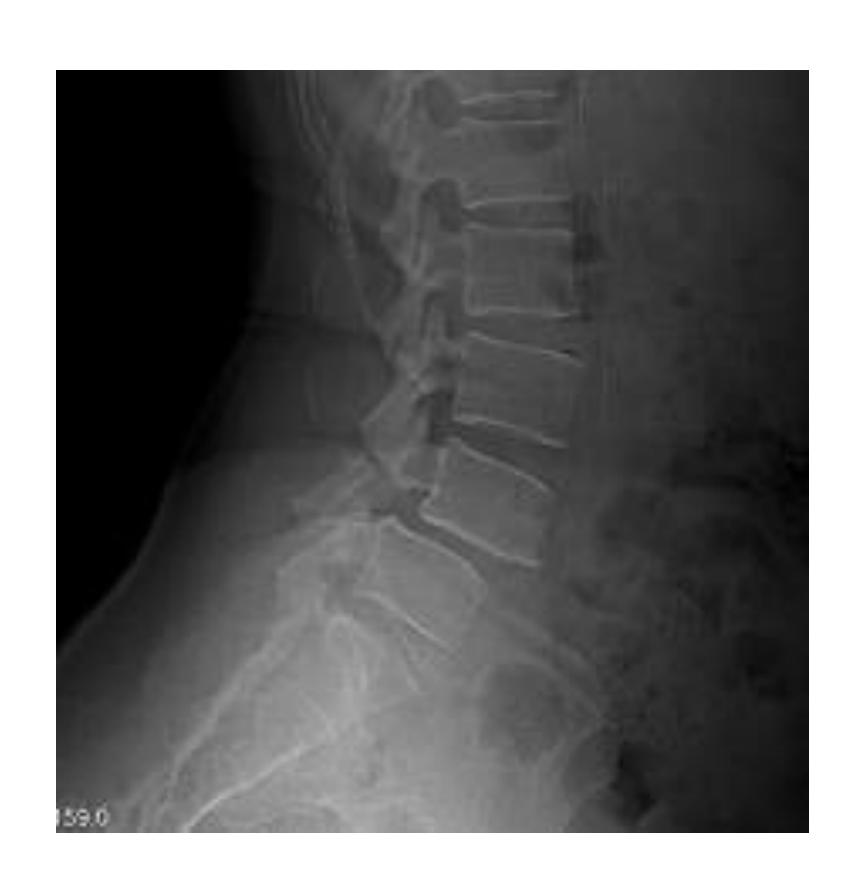

Spondylolisthesis

Lady came to the clinic complaining of long standing low back pain

Description Lateral x-ray of lumbar spine showing a fracture in the pedicle & slipped L4 over L5

Diagnosis: Spondylolisthesis

Diagnosis: Spondylolisthesis Next step? Oblique view - to see Scotty dog